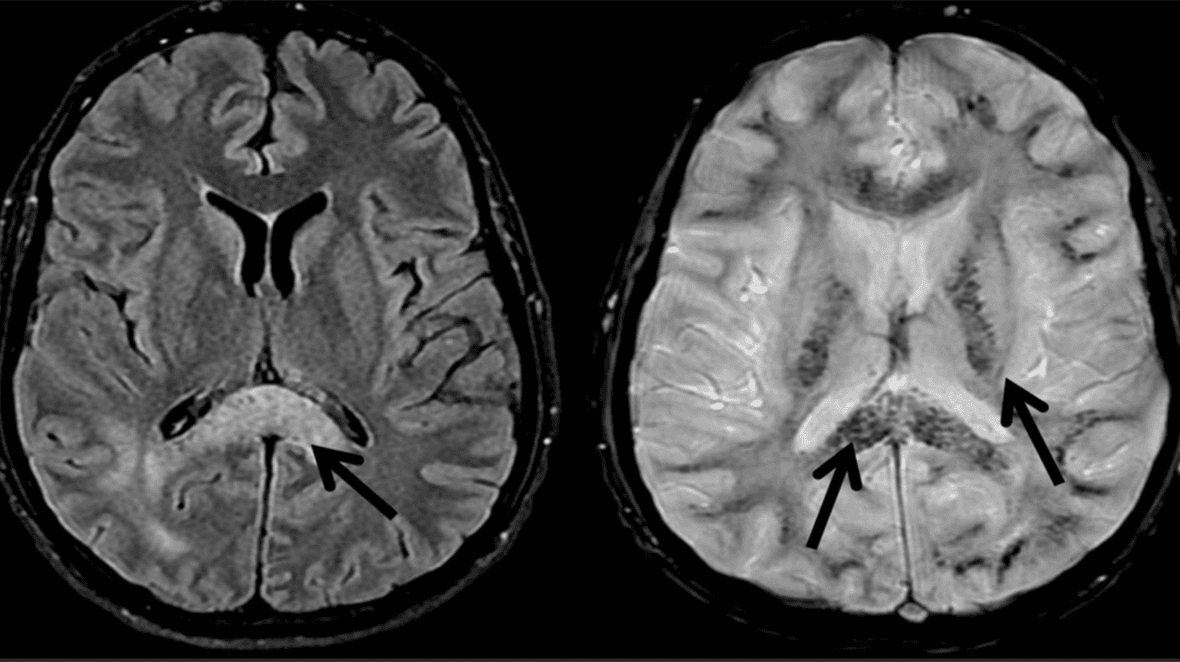

Da HACE muligvis at være en videreudvikling af svær AMS, har de to tilstande til dels den samme patogenese. Man ved ikke, hvorfor nogle patienter med AMS remitterer, og andre udvikler HACE. Individuel disposition og tilbøjelighed til HACE spiller muligvis en afgørende rolle. Ved MR-skanning har man fundet vasogent ødem, især i splenium i corpus callosum (Figur 2) [5]. Dette stemmer overens med de symptomer, som skade på splenium giver [10]. Vasogent ødem kan bekræftes måneder efter remission, hvor man har fundet hæmosiderin, et udtryk for en utæt af blod-hjerne-barriere (Figur 2). Ikke sjældent har man, ved obduktion eller røntgenundersøgelse af thorax, fundet lungeødem. Disse patienter har således haft både HACE og HAPE [4].